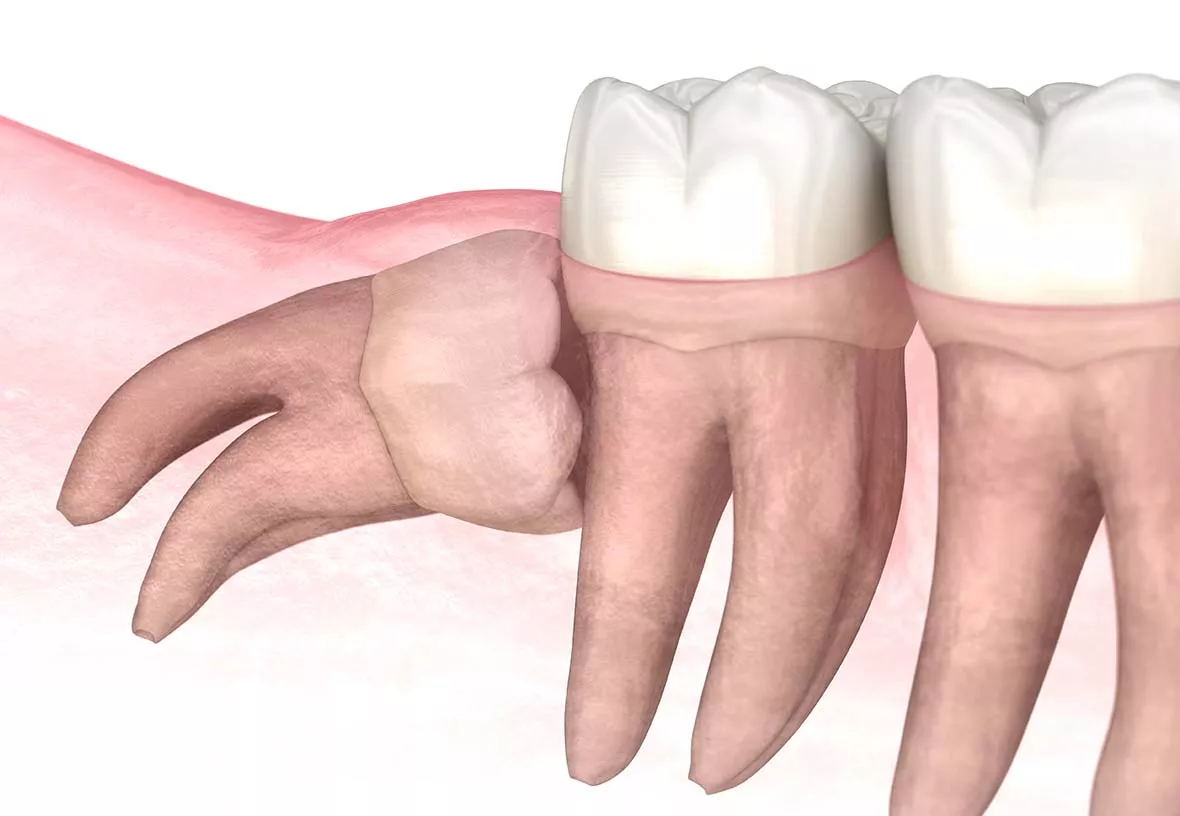

Your wisdom teeth are your last adult teeth. These large molars usually emerge behind your second set of molars at the back of your mouth. However, humans have evolved to have smaller jaws, and there is often not enough room in the jaw for the wisdom teeth to emerge correctly. When this happens, they can be crooked or grow under your other teeth and damage them. Your dentist will monitor the development of your wisdom teeth and recommend their extraction if they aren’t growing correctly.

The wisdom teeth are usually removed before they break through the gums. That means they need to be removed through surgery. Your dentist will make incisions near each tooth and then remove them. The treatment is done with a local anesthetic (freezing), and your dentist may also give you a mild sedative to help you stay relaxed during the procedure. After your wisdom teeth are removed, your dentist will close the incisions with sutures. You will need to return to your dentist’s office in about a week to have the sutures removed.